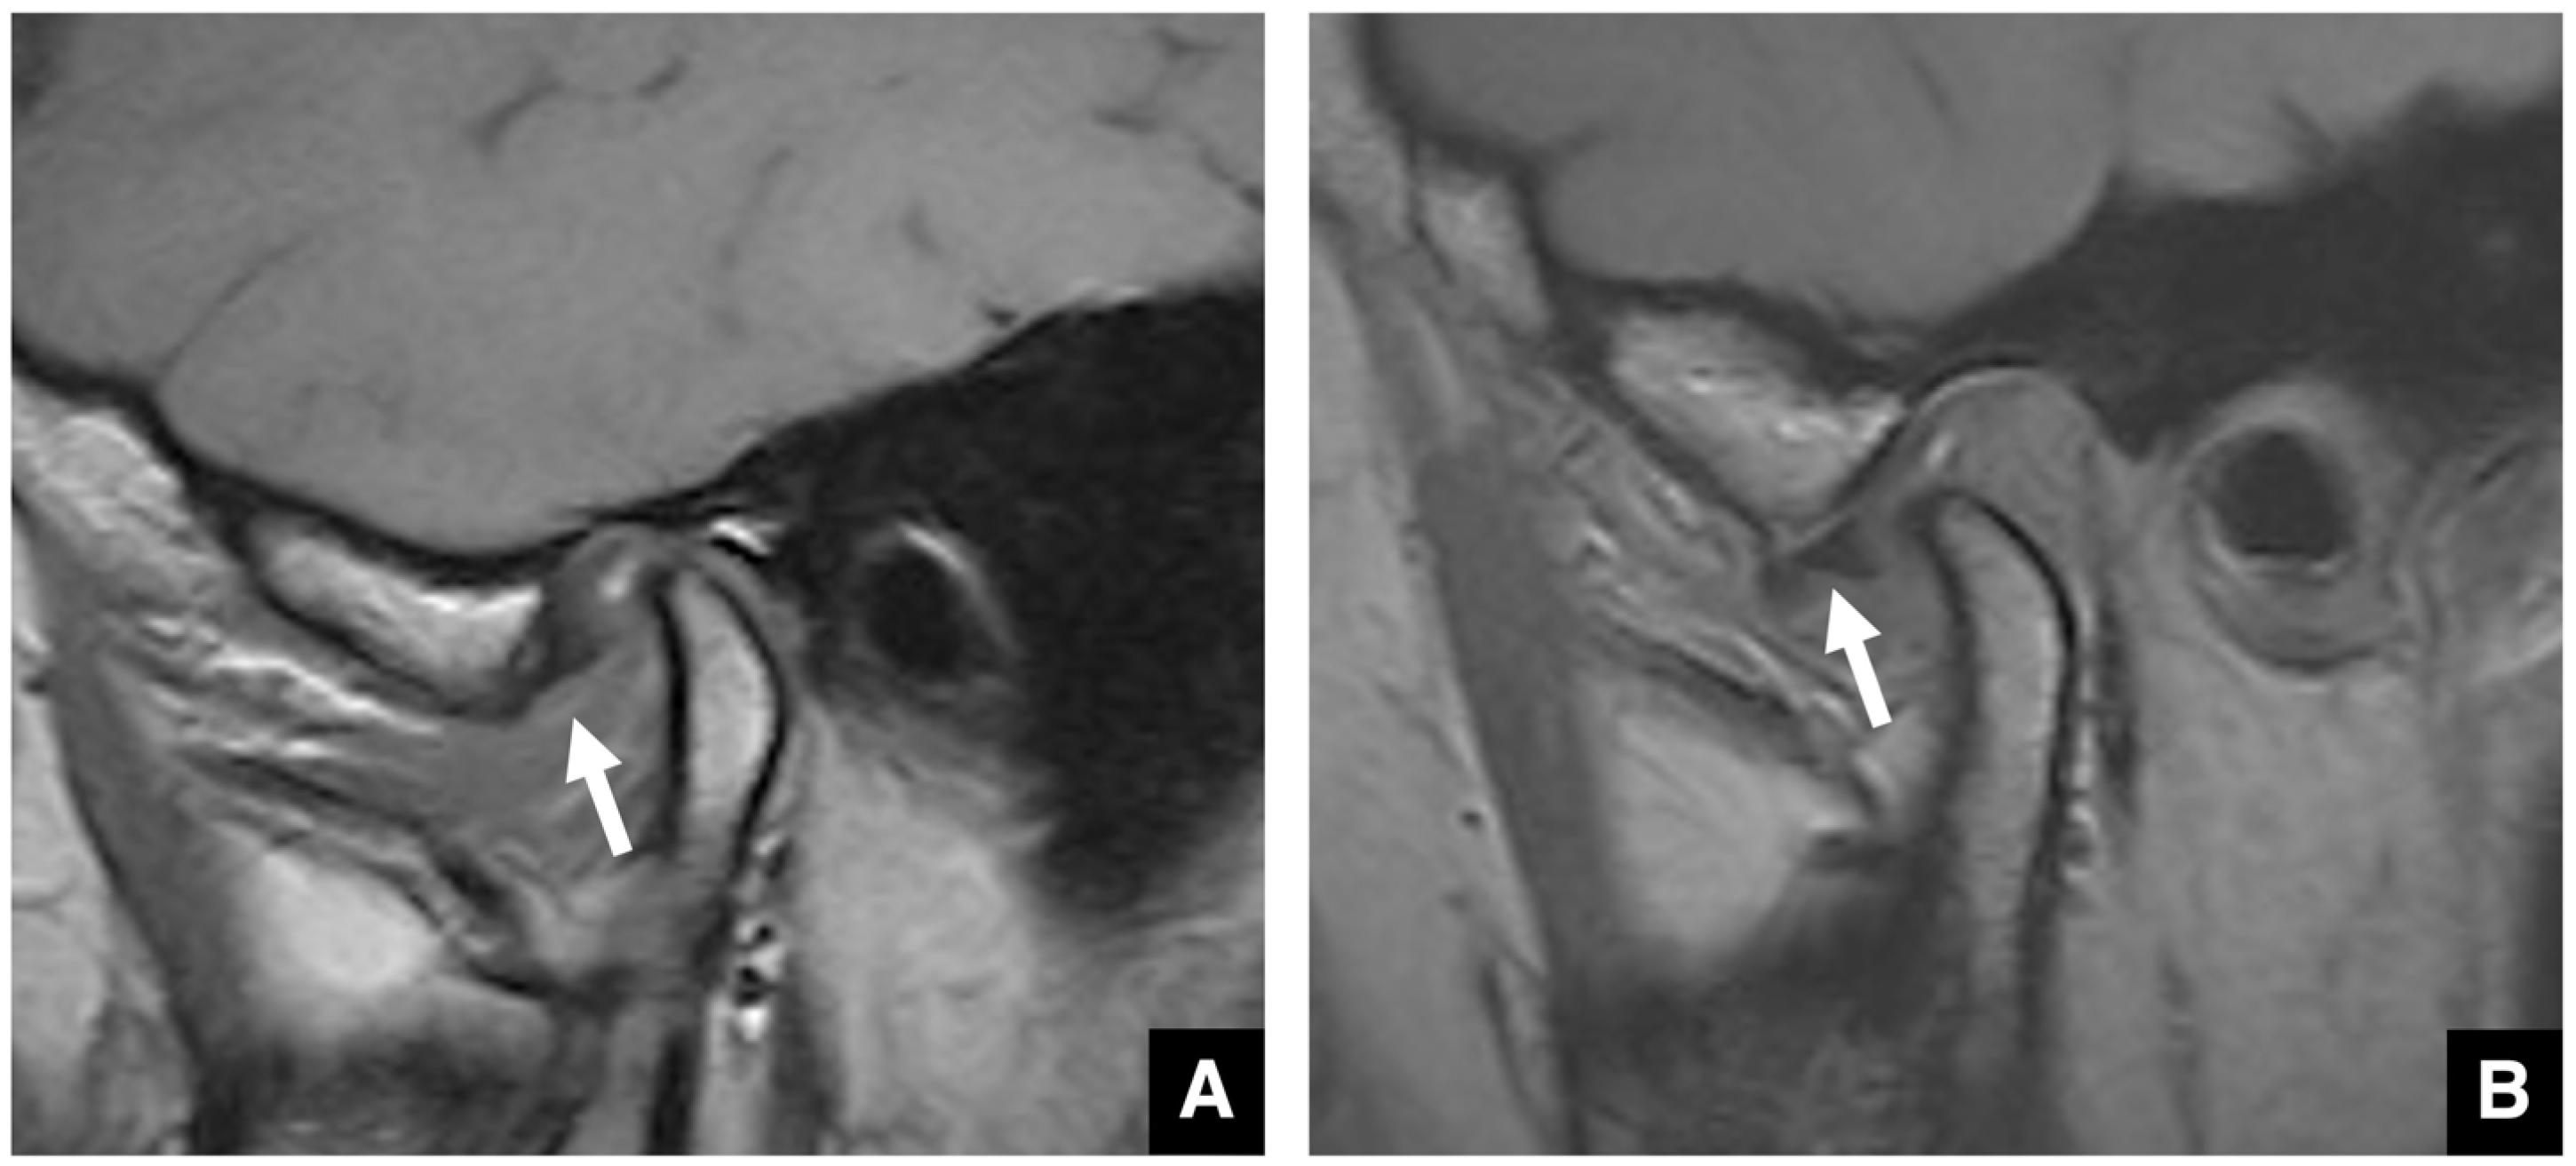

2.6. Imaging Evaluation of the TMJ in Jaw Deformities

- Morimoto, Y.; Tominaga, K.; Konoo, T.; Tanaka, T.; Ohba, T. Detection and significance of the characteristic magnetic resonance signals of mandibular condyles in children. Oral Surg. Oral Med. Oral Pathol. Oral Radiol. Endod. 2004, 97, 269–275. [Google Scholar] [CrossRef]

- Morimoto, Y.; Tominaga, K.; Konoo, T.; Tanaka, T.; Yamaguchi, K.; Fukuda, J.; Ohba, T. Alternation of the magnetic resonance signals characteristic of mandibular condyles during growth. Oral Surg. Oral Med. Oral Pathol. Oral Radiol. Endod. 2004, 98, 348–354. [Google Scholar]

- Morimoto, Y.; Konoo, T.; Tominaga, K.; Tanaka, T.; Yamaguchi, K.; Fukuda, J.; Ohba, T. Relationship between cortical bone formation on mandibular condyles and alternation of the magnetic resonance signals characteristic during growth. Am. J. Orthod. Dentofac. Orthop. 2007, 131, 473–480. [Google Scholar] [CrossRef] [PubMed]